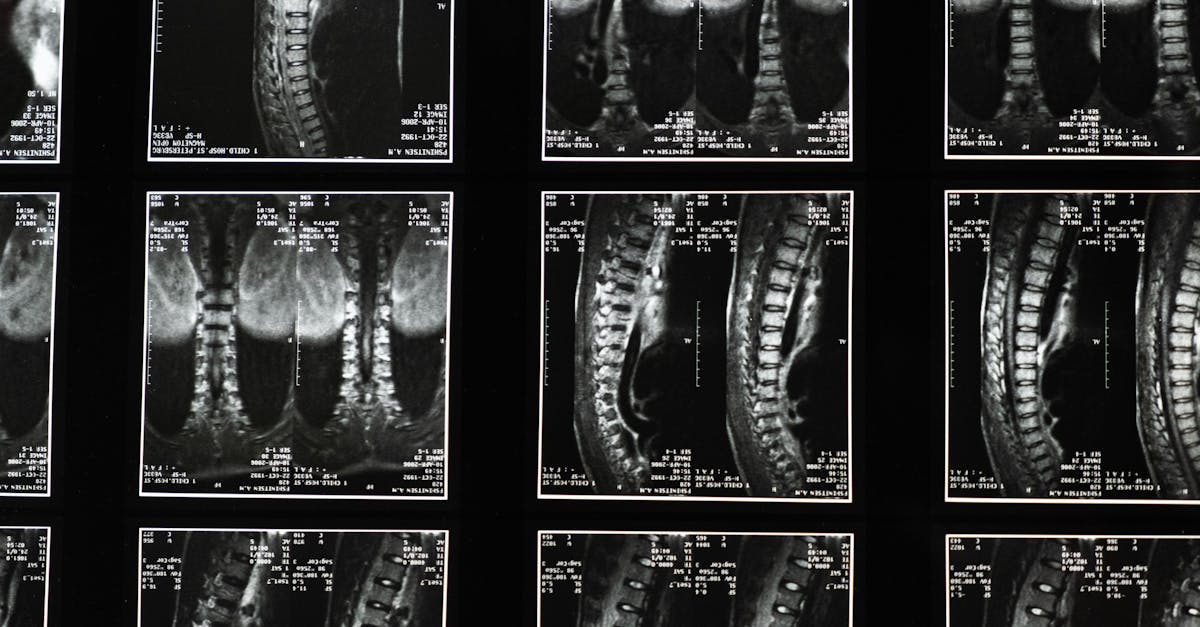

La décompression neurovertébrale agit en étirant les espaces entre les vertèbres, permettant ainsi de réduire la tension sur les structures environnantes. Cette technique aide à soulager la douleur et à améliorer la circulation sanguine. Les médecins et les praticiens utilisent cette méthode pour traiter divers problèmes, tels que les hernie discale, les bombement discal et la dégénérescence discale.

La décompression neurovertébrale est une technique thérapeutique qui consiste à soulager la pression exercée sur les racines nerveuses et les disques intervertébraux. Elle repose sur des méthodes douces qui favorisent l’auto-réparation du corps. En libérant les tensions accumulées, cette approche permet de diminuer la douleur et de restaurer la mobilité, offrant ainsi un chemin vers une vie plus active et moins limitée.

Le principe fondamental de la décompression neurovertébrale repose sur l’activation du processus naturel de guérison du corps. Par des étirements ciblés, la pression est libérée et la circulation sanguine est améliorée autour des zones lésées. Cela permet une meilleure irrigation des tissus et un apport optimal en nutriments essentiels à la guérison. De plus, cette technique réduit l’inflammation et aide à soulager des douleurs chroniques, ce qui en fait une solution précieuse pour les patients en convalescence.

La décompression neurovertébrale utilise une technique de traction douce qui étire et relâche la colonne vertébrale. Cela permet de réduire la pression sur les disques intervertébraux et les racines nerveuses, tout en favorisant un meilleur flux sanguin. En offrant un soulagement de la douleur, la décompression favorise également la récupération et améliore la mobilité, ce qui est crucial après une blessure vertébrale. Les patients peuvent ainsi retrouver une qualité de vie meilleure, en réduisant leur dépendance vis-à-vis des médicaments anti-douleur.